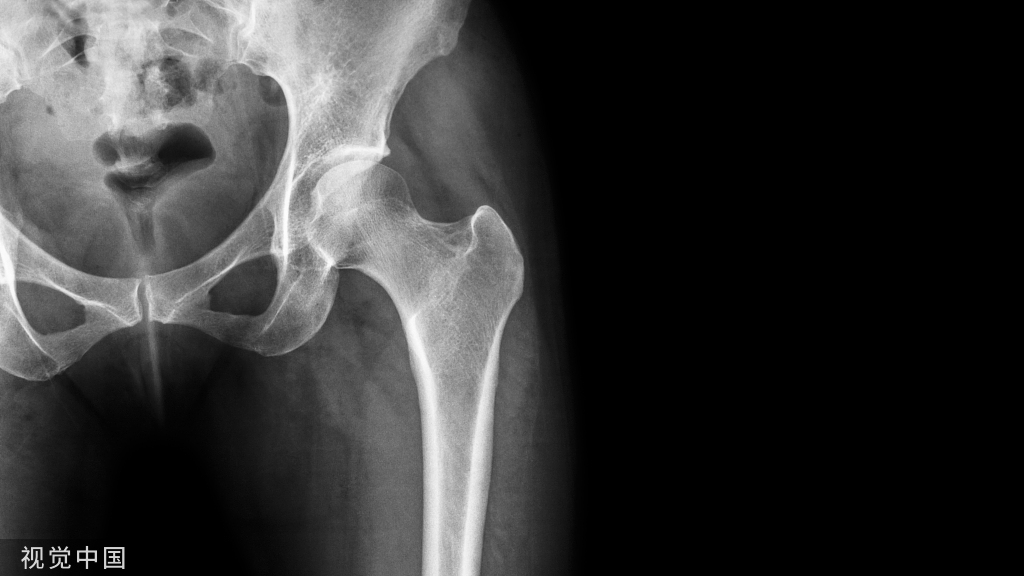

普通骨科疼痛部位图示